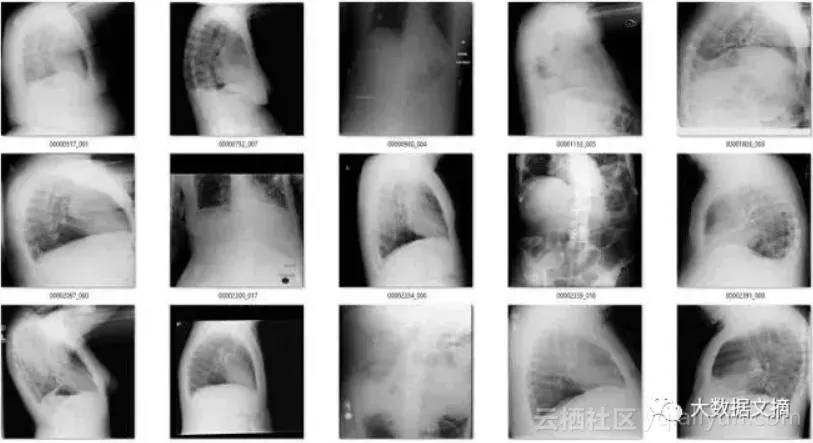

在余下的120个图像中,56个并不是正面胸片。其中主要包括了侧面胸片和腹部X光片,这也是我想要清理出去的异常图片。

那么其余的呢?有一些是经过混合的缩小图像(它们有着黑色或白色的大边界),因为过度曝光而变淡的图像(其中有一些图像整体都是灰色的),还有像素颜色完全翻转的图像等等。

结果很好!新的模型帮我找到了几百张侧面,腹部和骨盆X光图。

除了CXR14数据集本身的特点之外,我还注意到一件事,我的模型在幼儿的X光图上表现不佳。幼儿X光图本身和成年人X光图的区别很大,以致于它们被旋转检测器,反转检测器和错误身体位置检测器识别为“异常”。

因此,我认为我们的模型不应该考虑幼儿的X光图。好在患者年龄信息包含在X光图标签中,所以我们不需要借助深度学习来排除幼儿X光图。